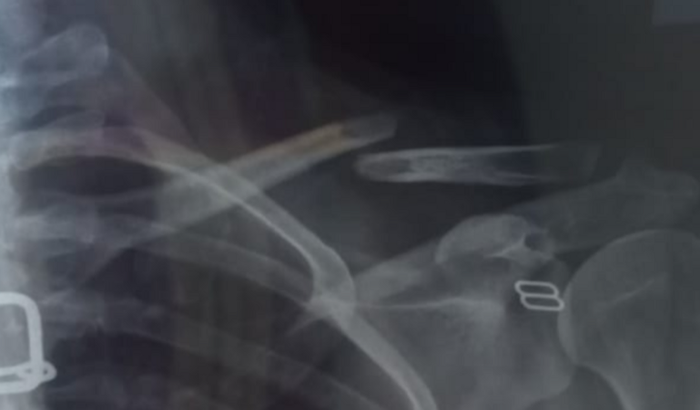

Cirugia de Emergência da clavícula

Eu Sônia Batista,sofri um acidente e fraturei a clavícula,preciso de uma cirúrgia de emergência.Gastos com procedimentos cirúrgico,despesas hospitalares,material síntese Placa de reconstrução 3,5 ver tudo

Eu Sônia Batista,sofri um acidente e fraturei a clavícula,preciso de uma cirúrgia de emergência.

Gastos com procedimentos cirúrgico,despesas hospitalares,material síntese Placa de reconstrução 3,5